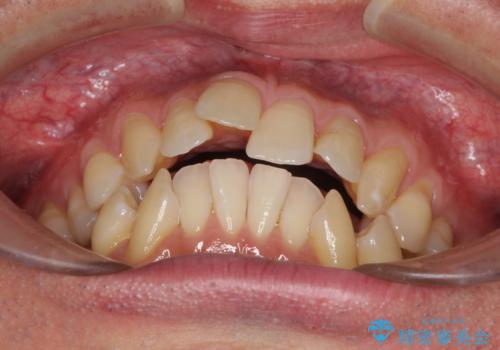

- 口元の閉じにくさと、前歯のでこぼこの歯並びを気にして来院された患者様です。

口元を積極的に引っ込めるために、上下左右の小臼歯計4本を抜歯することとしました。

叢生が強い場合、抜歯スペースが叢生を解消するために消費されるため、口元の突出感があまり改善されないことがあります。

今回の治療では、奥歯が前方に傾斜した歯並びだったため、奥に起き上がることで歯列が後方に移動し、横側からも口元が引っ込んだ感じが分かるほど改善されました。